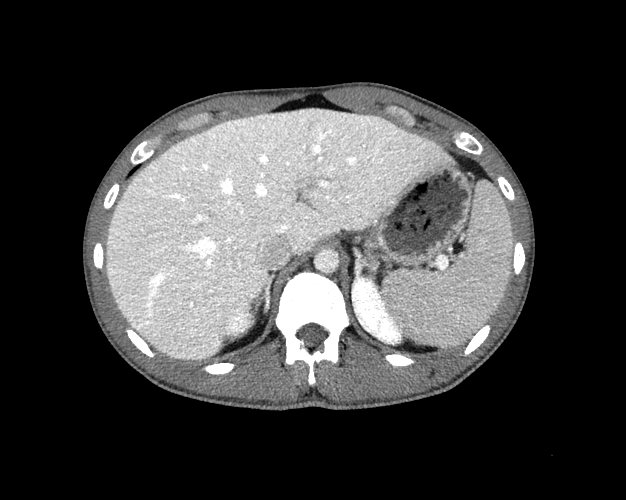

Body

Covers abdominal CT anatomy.